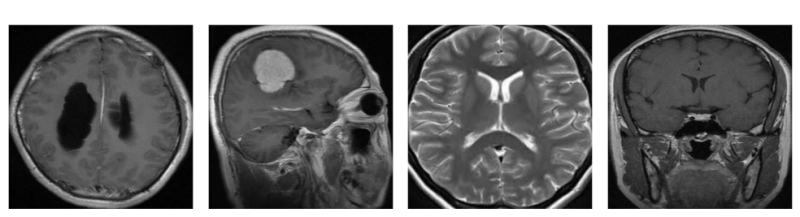

Everything you need to know about Github Jmejia22 Braintumorclassification Using Deep Learning To. Explore our curated collection and insights below.

We hope this guide on Github Jmejia22 Braintumorclassification Using Deep Learning To has been helpful. Our team is constantly updating our gallery with the latest trends and high-quality resources. Check back soon for more updates on github jmejia22 braintumorclassification using deep learning to.

- Brain Tumor Deep Learning